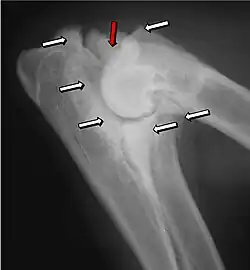

Most primary lesions are related to osteochondrosis, a disease of the joint cartilage, and osteochondritis dissecans (OCD), the separation of a flap of cartilage on the joint surface. Other common causes of elbow dysplasia include an ununited anconeal process (UAP) and fragmented or ununited medial coronoid process (FCP or FMCP).[1]

UAP is caused by a separation from the ulna of the ossification center of the anconeal process.[7] FMCP is caused by a failure of the coronoid process to unite with the ulna.